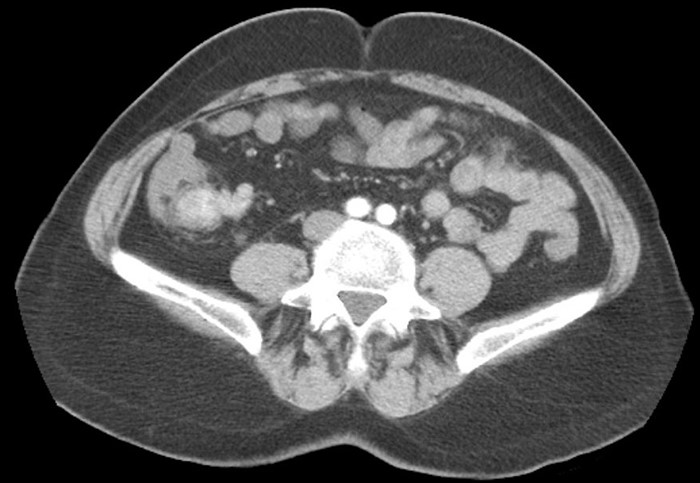

Immunohistochemical stains for Ki-67 showed staining in <1% of lesional cells. Computed tomography (CT) of the abdomen and pelvis was performed demonstrating an enhancing mass of the distal terminal ileum extending to the ileocecal valve, approximately 3.5x2cm in size with enlarged lymph nodes in the adjacent mesentery (Figure 3). There was no other evidence of disease. At laparotomy, the patient had a right hemicolectomy and terminal ileum resection with removal of the right and ileocolic arteries to the base in order to resect all draining lymph nodes. Careful visualization and palpation of the entire small bowel, mesentery and liver did not identify any other lesions.

Figure 3. Preoperative CT abdomen demonstrating enhancing terminal ileum carcinoid tumor with surrounding ileocolic adenopathy